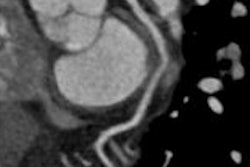

Combined dual-energy coronary CT angiography and CT myocardial perfusion imaging (CCTA-MPI) improves both the identification and discrimination of ischemia-causing coronary artery stenoses over CCTA alone, according to a Korean study presented at last week's RSNA meeting.

They used both DECT-MPI and CMR-MPI to look for the presence or absence of myocardial perfusion defects, while CCTA and invasive coronary angiography images were examined for the presence or absence of anatomically obstructive stenosis, defined as a stenosis greater than 50%.

Using electrocardiogram gating, the study team scanned the patients with a dual-source scanner (Siemens Healthcare) at 60% to 75% of the RR interval (140 kV and 100 mAs for the A tube; 80 kV and 165 mAs for the B tube). Scans began four minutes after adenosine infusion and followed injection of iodinated contrast using bolus tracking, Ko said.